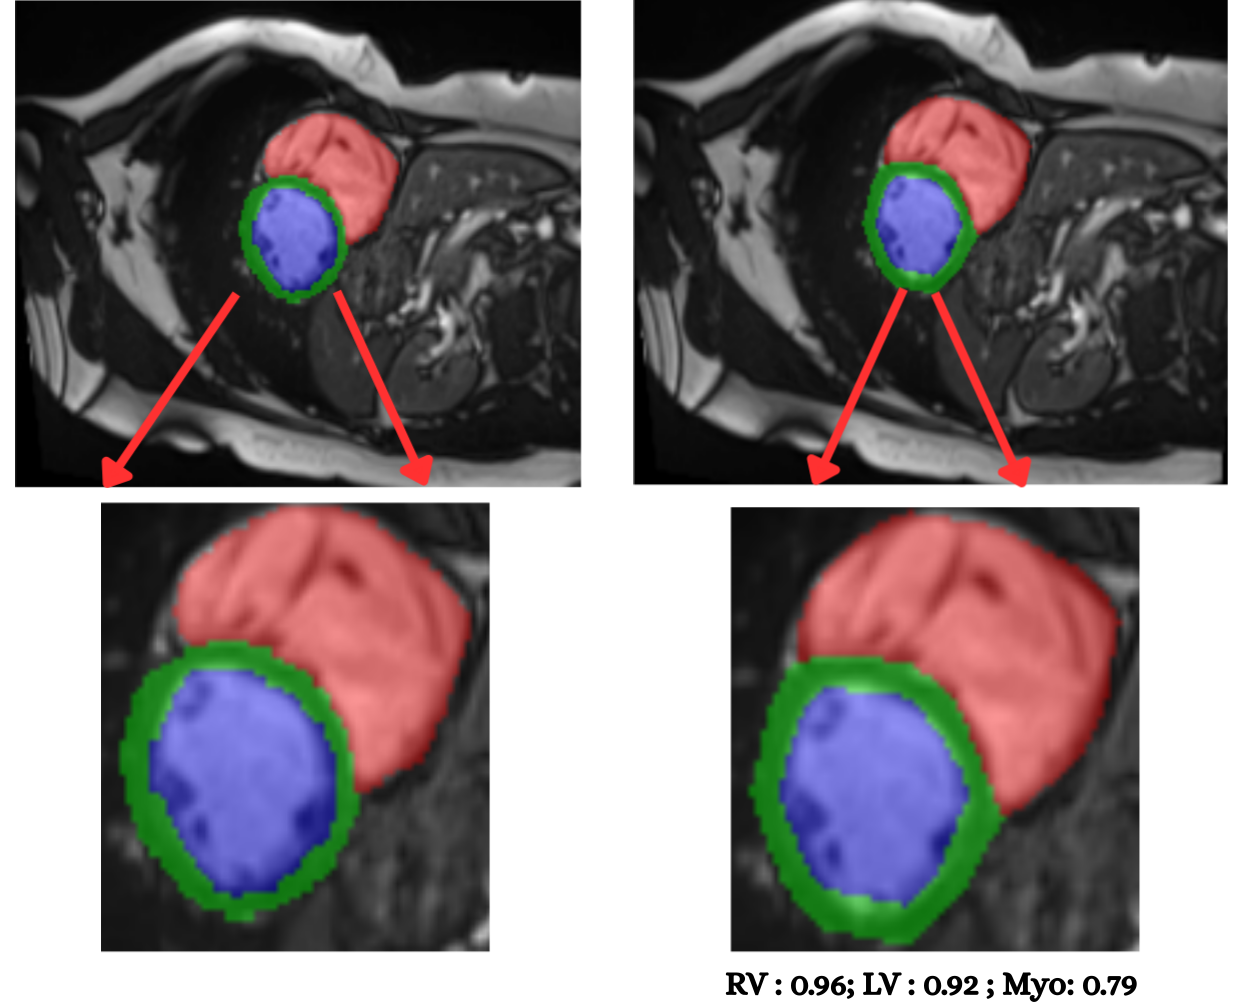

To evaluate cross–modality transfer, we perform few–shot fine tuning on the CAMUS echocardiography dataset, using only {5, 10, 20, 50} labeled samples from a single clinical site. Unlike MRI, ultrasound poses a significantly harder segmentation challenge due to acoustic artifacts, speckle noise, anisotropic contrast, and view–dependent anatomical deformation. Despite this domain gap, Figure 10 shows that PULSE progressively adapts to ultrasound geometry with increasing supervision. With only 5 labeled cases, the model produces coarse chamber boundaries and myocardium leakage, yet still recovers the global cardiac shape (mDice 0.612, mIoU 0.468). At 10 samples, segmentation accuracy improves substantially, with clear endocardial delineation and reduced basal drift (mDice 0.696, mIoU 0.556). Fine tuning on 20 cases leads to stable myocardium recovery (mDice 0.746), suggesting that the model internalizes modality–invariant structure once minimal supervision is available. At 50 cases, performance reaches near–MRI quality (mDice 0.815, mIoU 0.705), approaching full–data performance and producing visually crisp LV and RV walls even under ultrasound noise. These results demonstrate that PULSE can retain cardiac anatomical priors learned from MRI and rapidly transfer them to ultrasound with very limited supervisiona desirable property for deployment in low resource hospitals where complete annotation is rarely available. The smooth improvement across shots also reinforces the quantitative trend of Table 12, validating few–shot echocardiographic adaptation as a viable clinical pathway for real-world integration into emergency, bedside, and limited–annotation scenarios.